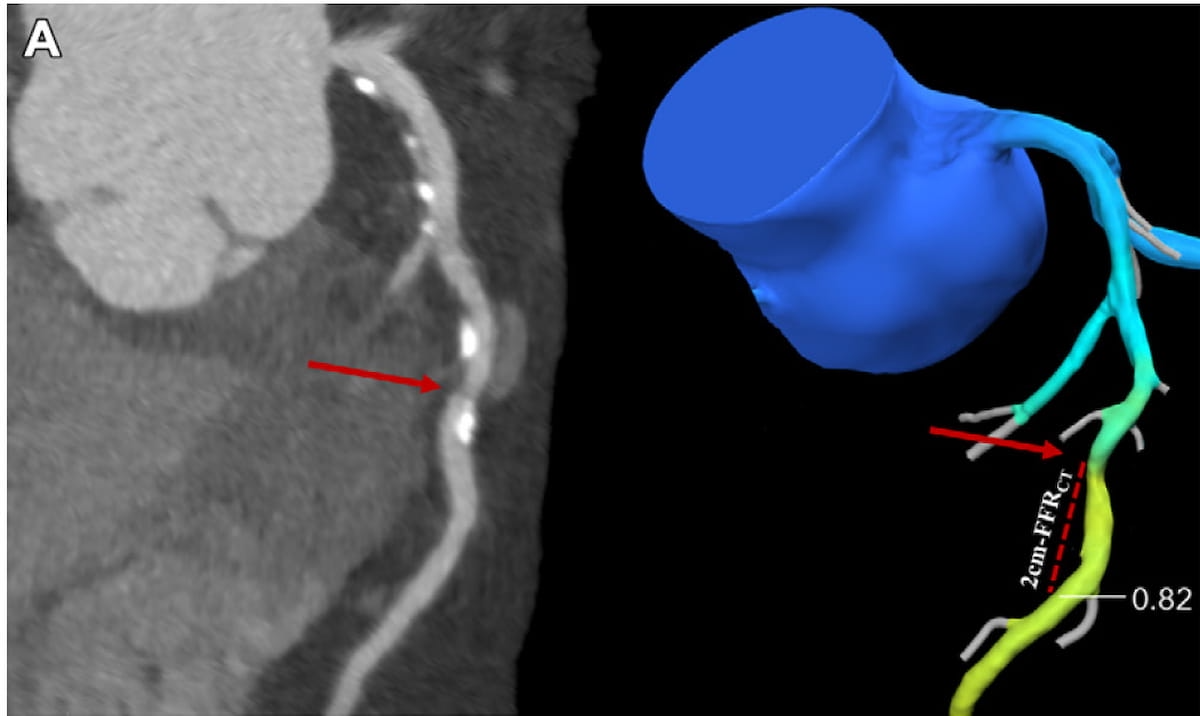

Abnormal findings on coronary computed tomography angiography-derived fractional flow reserve (CCTA-FFR) are associated with 3.2-fold higher risks of all-cause death or spontaneous myocardial infarction (MI) in patients with new-onset stable angina pectoris and coronary stenosis, according to newly published research.